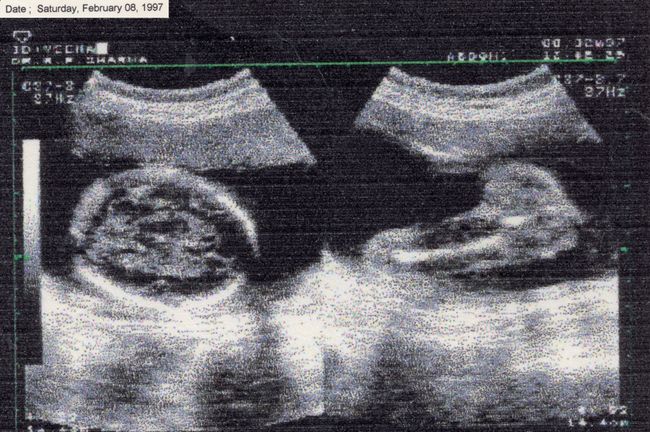

There Is No Other Home emerges from the space between chaos and understanding. My body often feels like it carries its own memory. My hands loose grip, I stumble more often, and I freeze at things others take for granted, like driving. I return to fragments of memory, my mother’s CT scan when she was carrying me and my twin sister, a childhood photograph, not as evidence of illness but as traces of fragility, endurance, and survival.